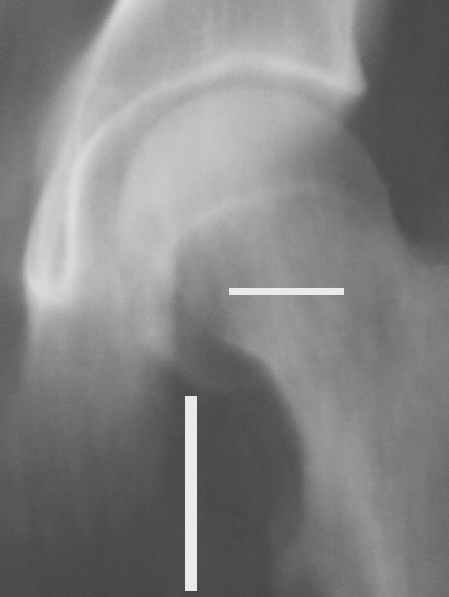

Уважаемые коллеги! Заканчивая обследование больного с переломо-вывихом бедра сделал ему обычные R-томограммы. Кажется удалось "поймать" и отломок и донорское место. Мои выводы - в скиаграмме. Считаю, что это передне-нижний фрагмент головки, образовавшийся вследствии отрывного перелома. На томограммах отломок обозначаю длинной стрелкой, а место откуда он оторвался - более короткой. Учитывая тот факт, что его размеры по КТ 25 х 15 мм считаю, что его фиксация на место необходима для профилактики артроза, что при 16-ти летнем возрасте пациента важно в плане максимального отодвигания эндопротезирования. Планирую оперировать его 24.05.05 г. Результаты представлю.

Несколько соображений к "картинкам". На прямом снимке и КТ-томограммах все типичные линии вертлужной впадины: крыша, передняя стенка, задняя стенка - сохранены. На КТ-сканах 6 и 7 появляется фрагментация головки. С учетом R-томограмм отломок расположен спереди-снизу, а не сзади-сверху от сустава, как написано в описании КТ.